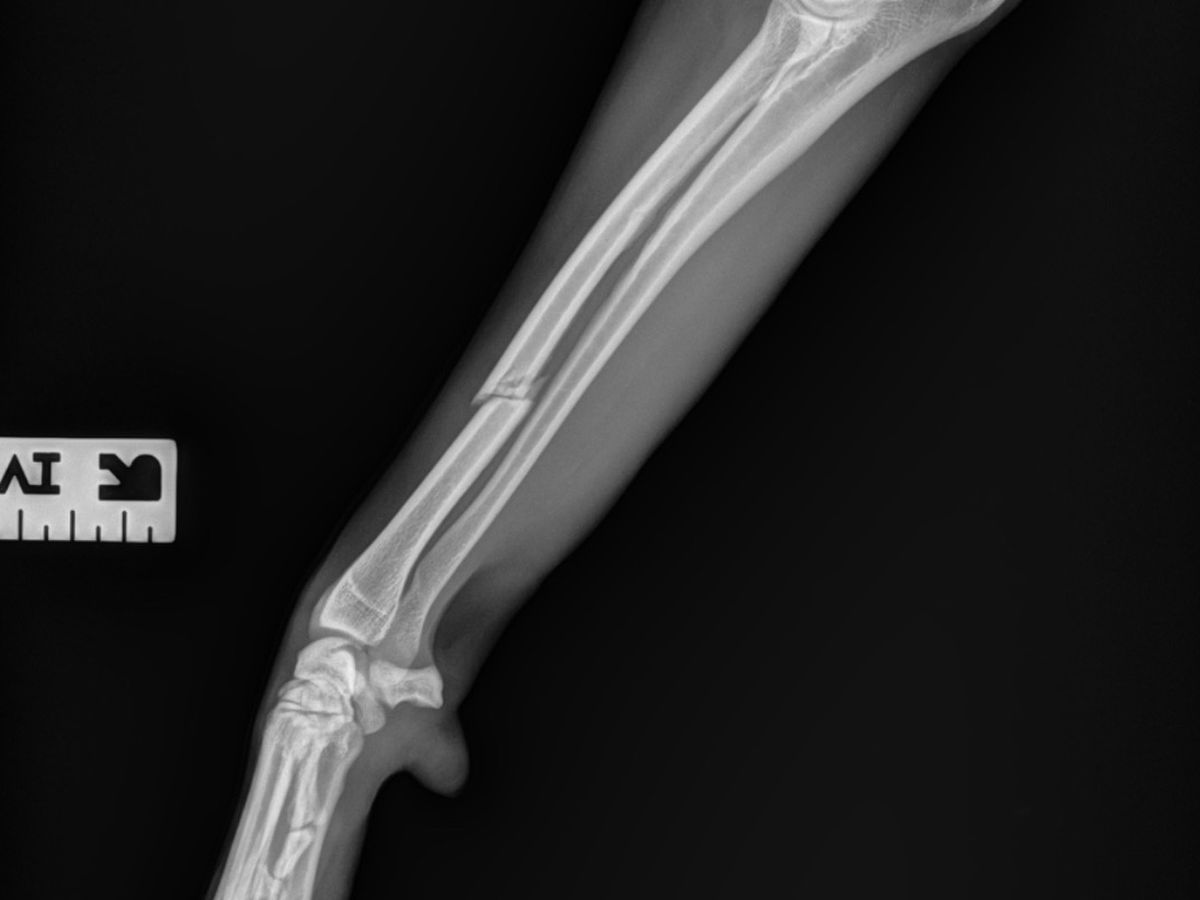

Unfortunately, my dog Boo got out of the house and my baby got hit by a car. Boo is stable, she has a cast and a few staples, but she will need surgery within the next week or two. We have been quoted by one pet hospital for between $5,000 and $8,000. We are currently coordinating with multiple hospitals to find a more affordable option for her surgery. An update on the exact amount will be posted once we find the right vet to do her surgery. My family is really struggling with money right now, so anything you can donate helps a lot. We appreciate your support ❤️